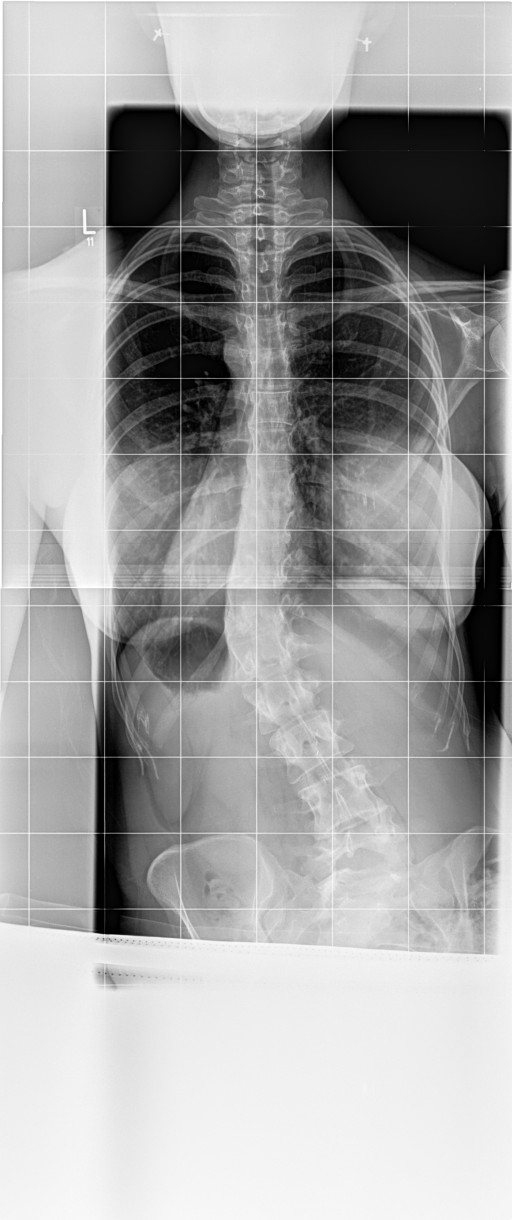

Diagnose: Skoliose LWS 41 Grad ( idiopathisch ) Kyphose 40 Grad

Bei mir steht der Brustknochen, bzw das Sternum total hervor ( siehe Bild , Datei ) In der Werner Wicker Klinik, sowie in Neustadt sagte man mir der vorstehende Brustknochen bzw das Sternum hätte nichts mit der Skoliose zu tun ?!? Aber die Wirbelsäule ist doch in sich verdreht, also hat es eigentlich doch etwas damit zu tun oder ? Vor 10 Jahren hatte ich diesen extremen Knochen nämlich noch nicht. Weis darüber jemand etwas ?

7.jpg

Aufnahme Herbst 2017

6.jpg